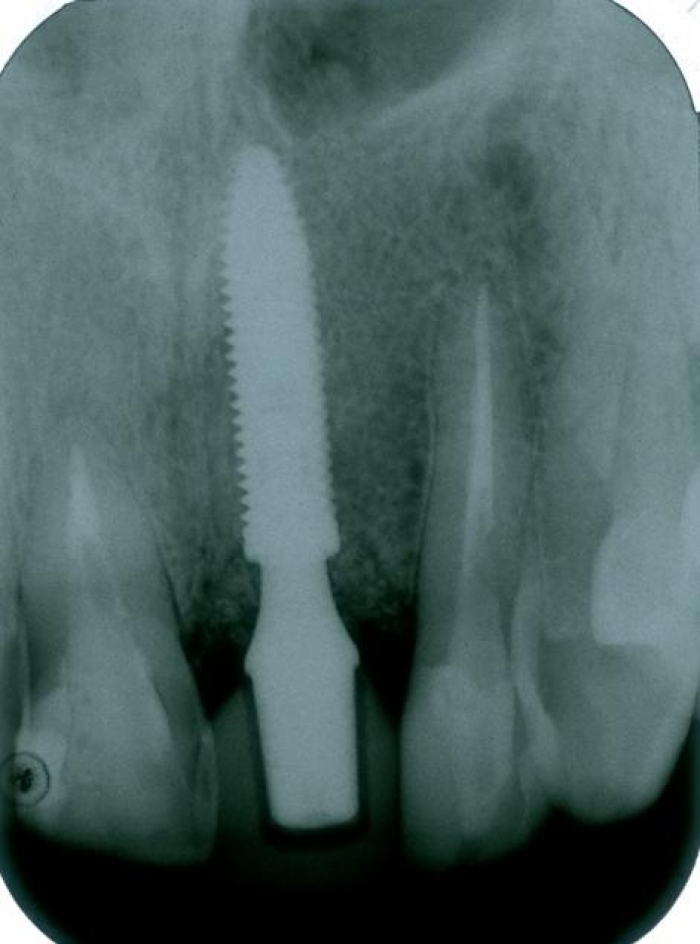

Raio x com prótese provisória fixa sobre implante